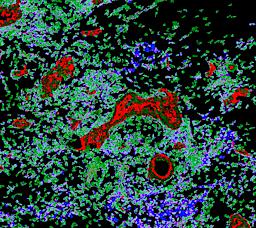

Pancreatic ductal adenocarcinoma is a lethal disease with limited treatment options and poor survival. We studied 83 spatial samples from 31 patients (11 treatment-naïve and 20 treated) using single-cell/nucleus RNA sequencing, bulk-proteogenomics, spatial transcriptomics and cellular imaging. Subpopulations of tumor cells exhibited signatures of proliferation, KRAS signaling, cell stress and epithelial-to-mesenchymal transition. Mapping mutations and copy number events distinguished tumor populations from normal and transitional cells, including acinar-to-ductal metaplasia and pancreatic intraepithelial neoplasia. Pathology-assisted deconvolution of spatial transcriptomic data identified tumor and transitional subpopulations with distinct histological features. We showed coordinated expression of TIGIT in exhausted and regulatory T cells and Nectin in tumor cells. Chemo-resistant samples contain a threefold enrichment of inflammatory cancer-associated fibroblasts that upregulate metallothioneins. Our study reveals a deeper understanding of the intricate substructure of pancreatic ductal adenocarcinoma tumors that could help improve therapy for patients with this disease.